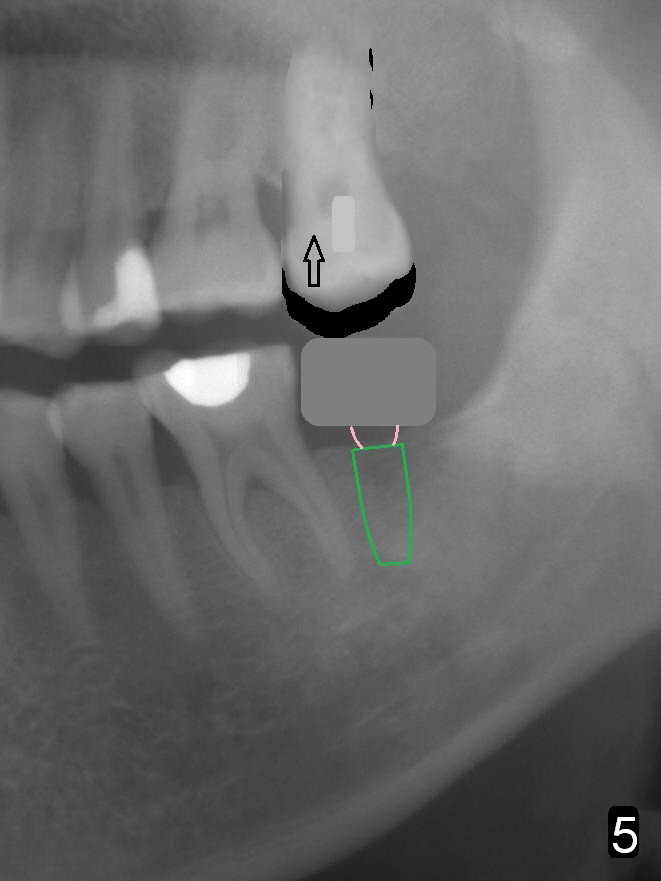

A 51-year-old man has lost #18 for more than 10 years (Fig.1,6). There appears to be sufficient bone height for implant (15 mm (Fig.7 (red dashed line: the superior border of the Inferior Alveolar Canal))). Prepare 4 mm implant spacer and SM starter drill and 2 mm pilot drill at 12 mm. Take PA. Palpation reveals that the edentulous ridge is wide. Place an implant in the middle of the ridge (buccolingually).

On second thought, Bicon implant is to be placed, either 4.5x8 or 5x6 mm (Fig.8).

In fact, the tooth 15 had basically no extrusion 6 years earlier (Fig.2) with even occlusal plane. When the tooth is intruded orthodontically, the occlusal plane may be not even (Fig.3). When the implant at #18 osteointegrates (Fig.4 green), fabricate a provisional (grey rectangle) with higher mesial occlusal surface. For certain period of time, the tooth #15 may change its axis so that the mesial portion of the tooth may be intruded more (Fig.5 arrow).